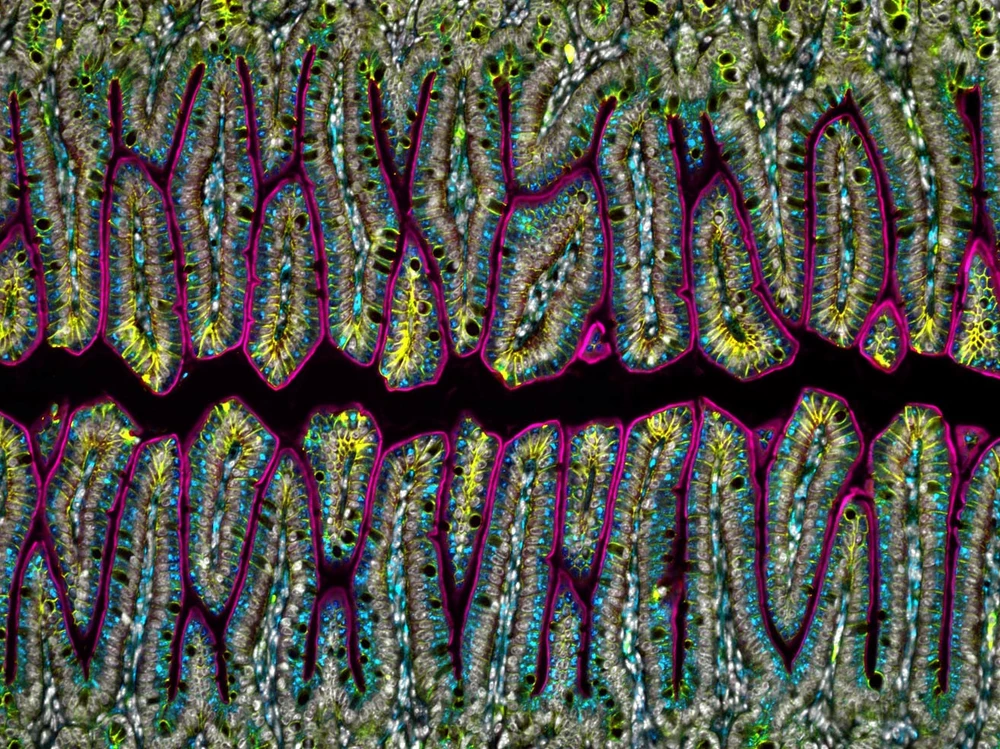

This image shows vertical slices, from top to bottom, through several villi from the small intestine of a mouse. The outer membranes of the intestinal villi are represented by solid-colored lines (1). The cells within the villi are represented by multicolored imperfect circles (2).

The small intestine – in mice and humans alike – is responsible for digesting the food we eat and absorbing its nutrients into the bloodstream to be distributed to the rest of the body. Nutrients are absorbed through a membrane on the inside of the intestinal wall. Villi can absorb nutrients through their tops, sides, and bases, dramatically increasing the area dedicated to nutrient absorption.

In a human, each villus is about 1 millimeter long, or roughly 13 times the width of a human hair.

These images were created using fluorescence microscopy.

Amy Engevik, Medical University of South Carolina